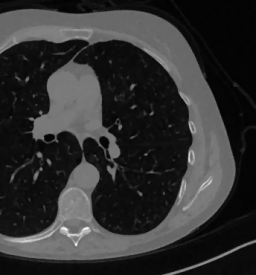

As real patient images, we have downloaded the widely used AAPM Low Dose CT Grand Challenge data set by the Mayo Clinic [35]. The considered images are 512×512512512512\times 512 pixel reconstructions of human abdomen, computed from full-dose acquisitions. In Figure 2 we depict one image with two zooms-in highlighting areas with different anatomical structures, such as pulmonary details, sections of ribs and low-contrast inter-costal muscles. In all the experiments reported in 5.1, we have used the images from the data set as ground truth xGTsubscript𝑥𝐺𝑇x_{GT} references. Coherently, we simulate the tomographic projections of the ground truth images, according to a 2D fan-beam geometry, and we add to the sinograms white Gaussian noise with 102superscript10210^{-2} noise level. To address sparse-view CT reconstructions, we considered two different protocols: the first one is a full angular acquisition with 1-degree spaced projections (we call it P360,360subscript𝑃360360P_{360,360} in the following); in the second one the scanning trajectory covers 180180180 degrees and computed only 606060 projections (it is labelled as P180,60subscript𝑃18060P_{180,60}).

Figure 2: A ground-truth image from the Low Dose Mayo data set, with two zoomed crops on regions with different anatomical structures.